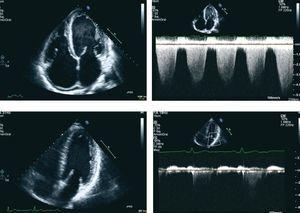

Sr. Director: Presentamos el caso de un hombre de 36 años con insuficiencia renal crónica e hipertensión secundaria a una glomerulonefritis crónica no biopsiada. Se realizó una fístula arteriovenosa (FAVI) y 6 meses después, en agosto de 2007, precisó el inicio de tratamiento sustitutivo tipo hemodiálisis. El ecocardiograma (ECOCG) realizado el 22 de agosto de 2007 no presentó hallazgos de significación patológica (ligera hipertrofia ventricular izquierda, ausencia de anomalías valvulares, competencia valvular y buena función sistólica con estudio de estrés negativo para isquemia). Seis meses después del inicio de diálisis comenzó disnea progresiva, opresión torácica y mala tolerancia a la diálisis, por lo que se inició hemodiálisis diaria. Entre otras pruebas se realizó de nuevo un ECOCG en febrero de 2008 en el que destacaban una disfunción sistólica del ventrículo izquierdo (fracción de eyección [FE] visual del 40%, volumen telediastólico [VTD] 157 mm, volumen telesistólico [VTS] 105 mm), una ligera dilatación de la aurícula izquierda con insuficiencia mitral ligera-moderada e hipertensión pulmonar severa. Se repitieron nuevos ECOCG en agosto y septiembre de 2008, observándose deterioro de la función sistólica hasta de un 25%, pérdida de la configuración ventricular con aumento del VTD a 185 ml, grado severo de insuficiencia mitral funcional con mayor dilatación auricular y aumento del grado de hipertensión pulmonar (figura 1). En noviembre de 2008 el paciente fue sometido a un trasplante renal con buena evolución, y la creatinina en el momento al alta era de 1,5 mg/dl. Durante el posoperatorio se decidió realizar el cierre de la FAVI. Durante los meses posteriores al trasplante el paciente ha continuado asintomático, con mejoría en los parámetros del ECOCG realizado en julio de 2009: desaparición completa de la insuficiencia mitral, VTD de 129 ml y FE del 45% (figura 1).

Figura 1. Eco bidimensional (A y B), apical dos cámaras, que muestra la evolución del tamaño y el volumen de las distintas cavidades. En las imágenes de Doppler continuo (C y D) se observa la práctica desaparición de la insuficiencia mitral tras la realización del